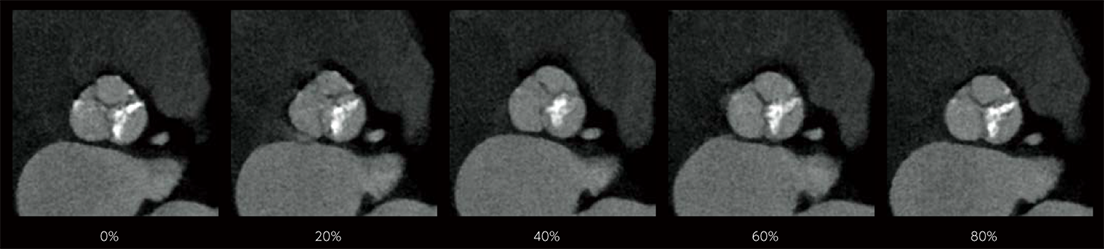

Dans les examens TDM cardiaques, les différents facteurs tels que la fréquence cardiaque et les mouvements du cœur affectent la qualité de l’image. Avec les méthodes conventionnelles de reconstruction d’image, des artères coronaires non focalisées et des artefacts causés par le mouvement peuvent apparaître, ce qui se traduit par des images ne répondant pas à la qualité attendue, ce qui peut affecter le diagnostic. Pour résoudre ces problèmes, Fujifilm a développé Cardio StillShot, qui calcule la direction et la quantité de mouvement du sujet en quatre dimensions à partir des données brutes collectées pendant les examens TDM cardiaques, et les corrige pendant la reconstruction de l’image pour obtenir une résolution temporelle effective de 28 msec.*1 La résolution temporelle effective contribue à améliorer la capacité de diagnostic en fournissant des images cliniques focalisées de haute définition avec moins d’artefacts de mouvement, même chez les patients ayant une fréquence cardiaque élevée.

Cardio StillShot : OFF

Cardio StillShot : ON